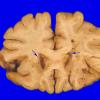

PERIPHERAL NEUROPATHY

10 INFECTION

2 Cytomegalovirus (in AIDS)